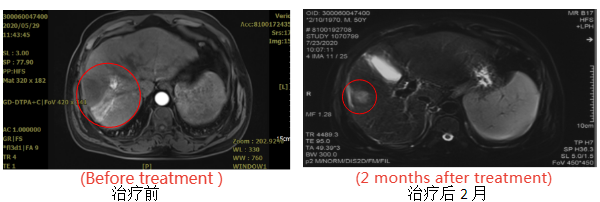

Patient, male, 50 years old, with primary liver cancer, staged as cT3bN0M0 (stage IIIb), Child-Pugh class A.